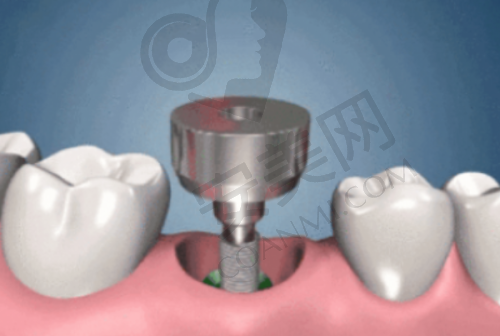

特别多患者可能会疑惑,为什么韩国登腾种植牙的价格是3380元起呢?其实,这个价格只是一个基础价格。在实际的种植过程中,会受到多种因素的影响。首先,患者的口腔状况是一个重要因素。如果患者的牙槽骨条件较好,种植手术相对简单,费用可能就会接近基础价格。但如果患者存在牙槽骨吸收、骨量不足等问题,就需要进行额外的骨增量手术,这会增加治疗的费用。其次,种植体的型号和规格也会影响价格。不同的型号和规格适用于不同的口腔情况,价格也会有所差异。此外,医院的技术水平、服务质量等因素也会对价格产生一定的影响。福州登特口腔医院凭借其专精的技术和优质的服务,在确保治疗成效的同时,为患者提供了相对合理的价格。

柳书喻院长在种植牙治疗中始终坚持个性化定制的理念。他认为每个患者的口腔情况都是独特的,因此需要制定个性化的种植方案。在治疗前,柳书喻院长会对患者进行全方面的口腔检查,包括口腔X光片、CT扫描等,了解患者的牙槽骨情况、牙齿缺失情况等。然后,根据患者的具体情况,为患者选择合适的种植体型号和规格,并设计出更适合患者的种植方案。在手术过程中,柳书喻院长会凭借不错的技术,确保种植体的正确植入,为患者的治疗成效提供保护。这种个性化定制的理念,能够让患者获得更加满意的治疗成效。